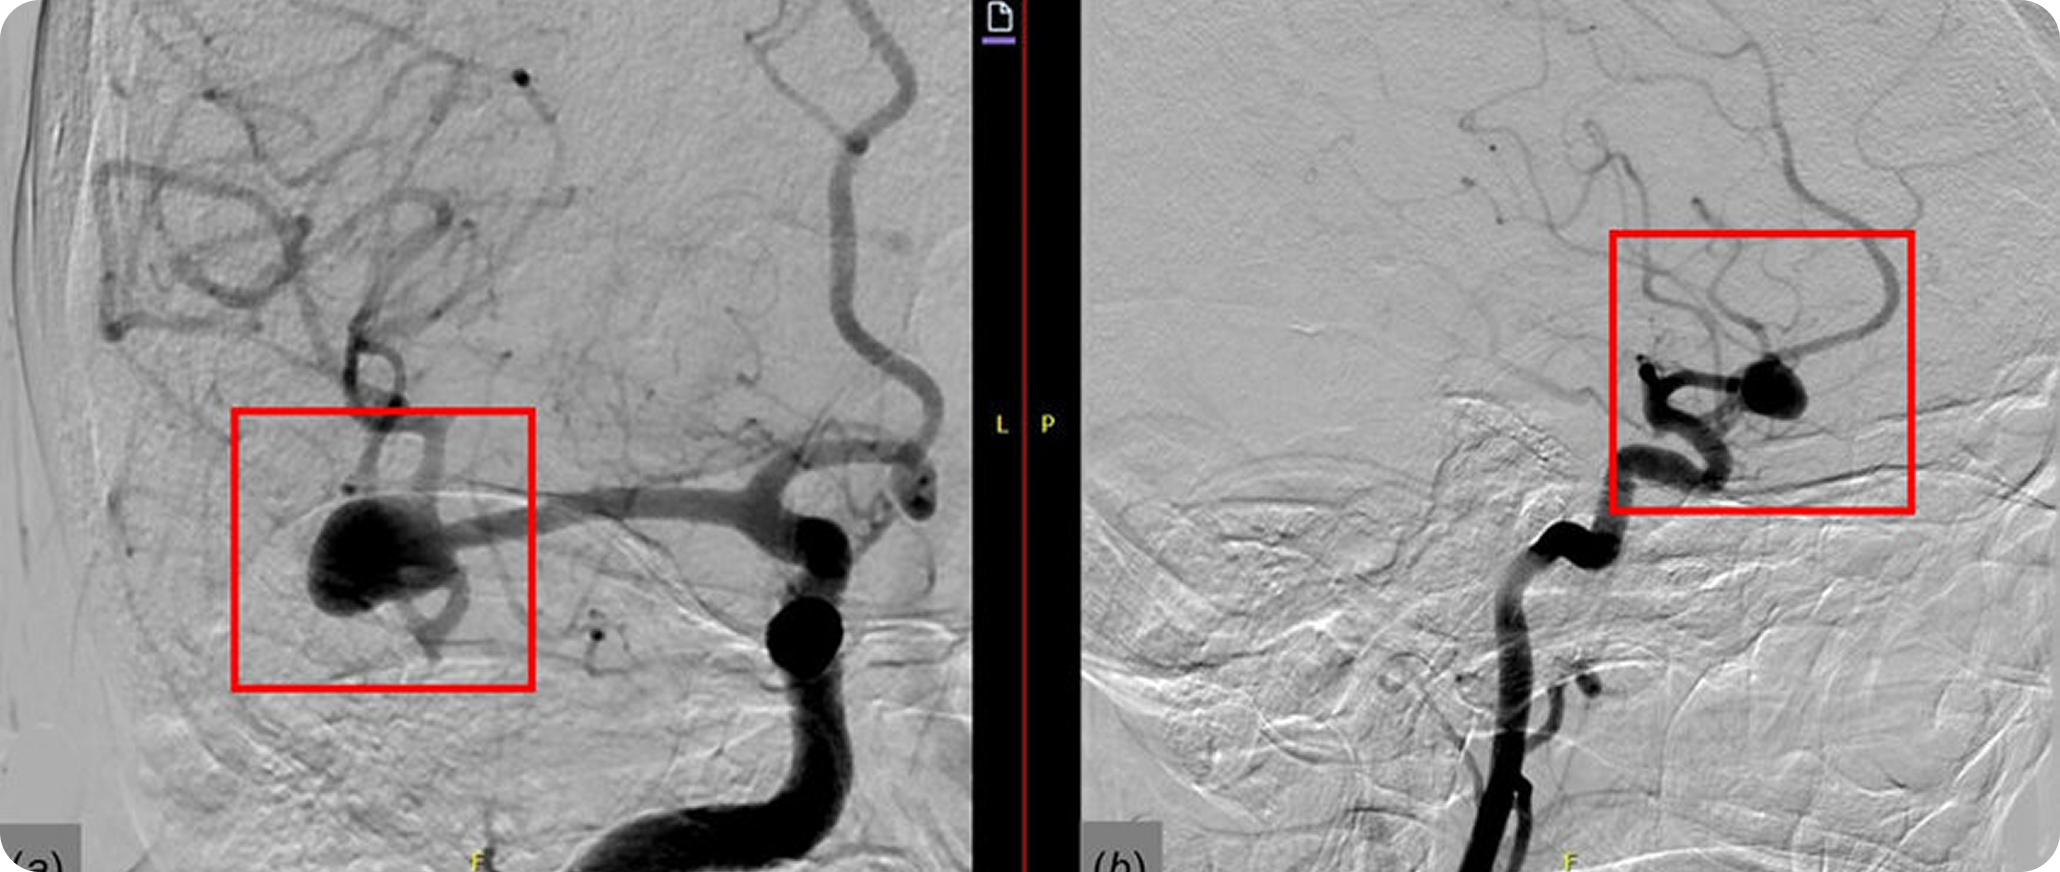

A planning procedure identifies blood vessels supplying the liver tumor.

Tiny radioactive beads are delivered through a catheter into tumor-feeding vessels.